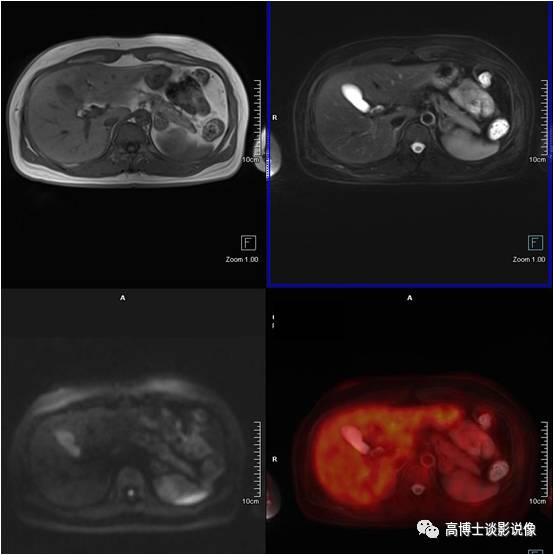

髓样(质)脂肪瘤

中年女性,左侧肾上腺见一大小约1.9cm×2.1cm的类圆形异常信号灶,信号不均匀,内含脂肪信号,考虑为髓样脂肪瘤。

点评:

本病很少出现临床症状,多在体检时偶然发现。如肿瘤较大压迫邻近组织器官或瘤内出血坏死,可引起不适症状。但对于直径较小且无临床症状者应随访观察。